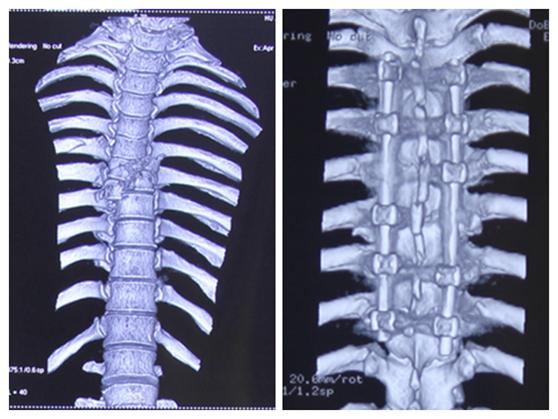

随后,李维新教授紧急对患者行“全麻下后中正肌间隙入路胸椎体爆裂性骨折复位神经减压植骨融合内固定术”。术后,王先生症状缓解明显,约两周后即出院调养。

手术前后对比

“我们通过脊间隙制钉把脊柱完全复位了,而且对这个脊髓进行了一期的减压,减除脊髓致压物,很大程度保留脊髓功能。”李维新教授回忆“术中我们看到脊髓搏动是恢复的,而且患者脊髓复位也非常好。”

术后,经过两周的恢复,患者血气胸也逐渐好了,大小便功能恢复、肢体运动也逐渐恢复。